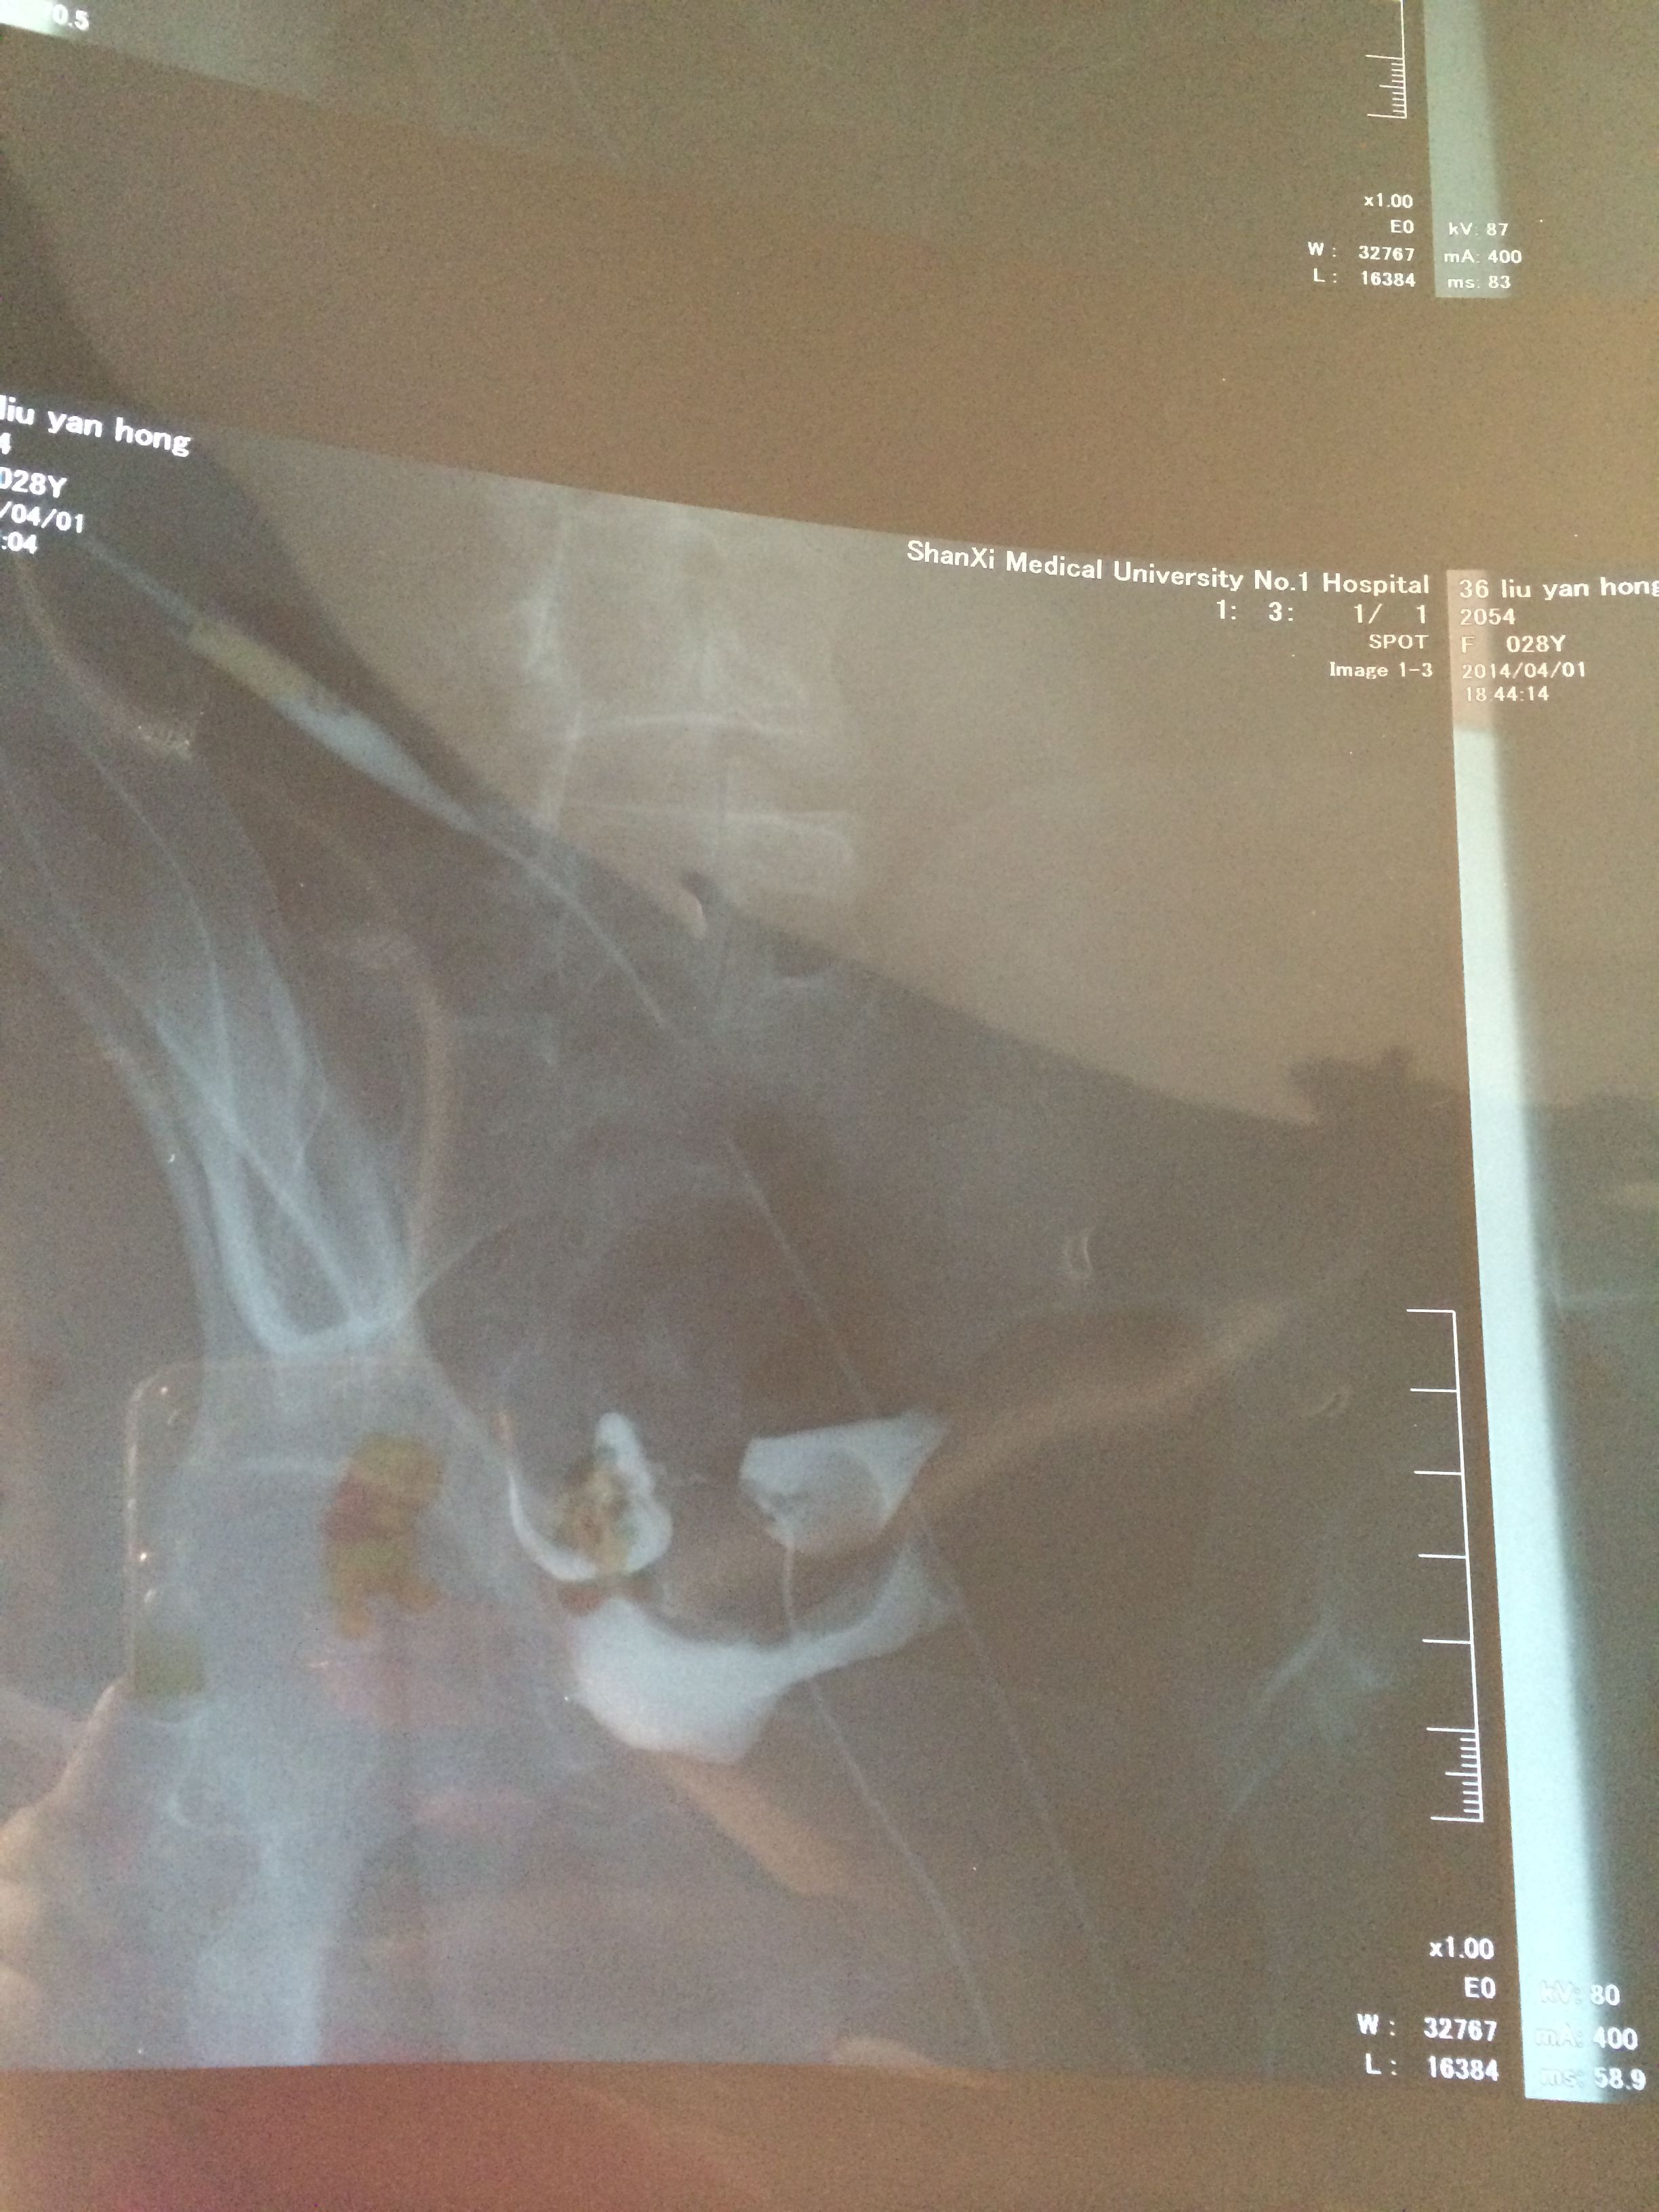

上个月做了造影,显示输卵管左侧不通,右侧通,我想让大夫帮我看一下通的那侧输卵管好不好,能不能正常受 孕?该怎么治疗? 点击展开 母婴用户72774049 2014-05-13 15:59 为您推荐: 其他回答 病情分析: 你好,双侧卵巢一旦出现第一个卵子成熟别的就都停止发育退化消失。 指导意见: 你这情况也可以怀孕就是几率较低,建议输卵管通水治疗。 匿名用户 2014-05-13 16:06 相关问题 你好,我刚做完输卵管造影,左侧输卵管侧地不通,右侧通但是有些炎症,可以怀孕吗? 我之前做过输卵管不通,月经6月11号来的 24号上午打的排卵针,24 25 26晚上有同房好不好怀 我之前做过输卵管不通,月经6月11号来的 24号上午打的排卵针,24 25 26晚上有同房好不好怀